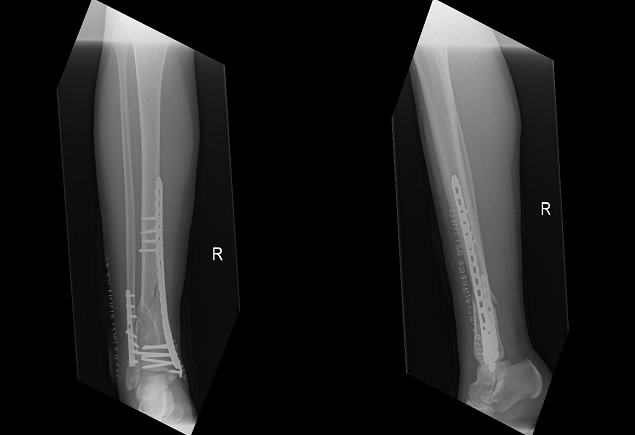

A 23-year-old healthy male presented to the accident & emergency department complaining of pain in the right lower leg and ankle following a trivial twisting injury to the right ankle while training in the gym. On examination, the patient had severe pain and mild swelling to the right lower leg and ankle with no visible deformity, normal skin condition and intact distal neurovascular status. Initial radiologic examination revealed a distal third tibia and fibula long oblique displaced fractures that were associated with a roughly 3cm x 2cm well-defined exapnsile, lobulated and lytic lesion with hypersclerotic margins and a narrow transitional zone (Figure 1). Routine laboratory investigations including a complete blood count, liver function test and renal function test did not reveal any abnormalities. An initial diagnosis of pathological fracture with a differential diagnosis of non-ossifying fibroma versus chondromyxoid fibroma was, therefore, made. The patient was, accordingly, planned for bone curettage and primary fixation of the distal tibia and fibula.

Figure 1 Initial injury AP and lateral x-rays - distal tibia and fibula fractures with an associated expansile, lobulated and lytic lesion with hypersclerotic borders.